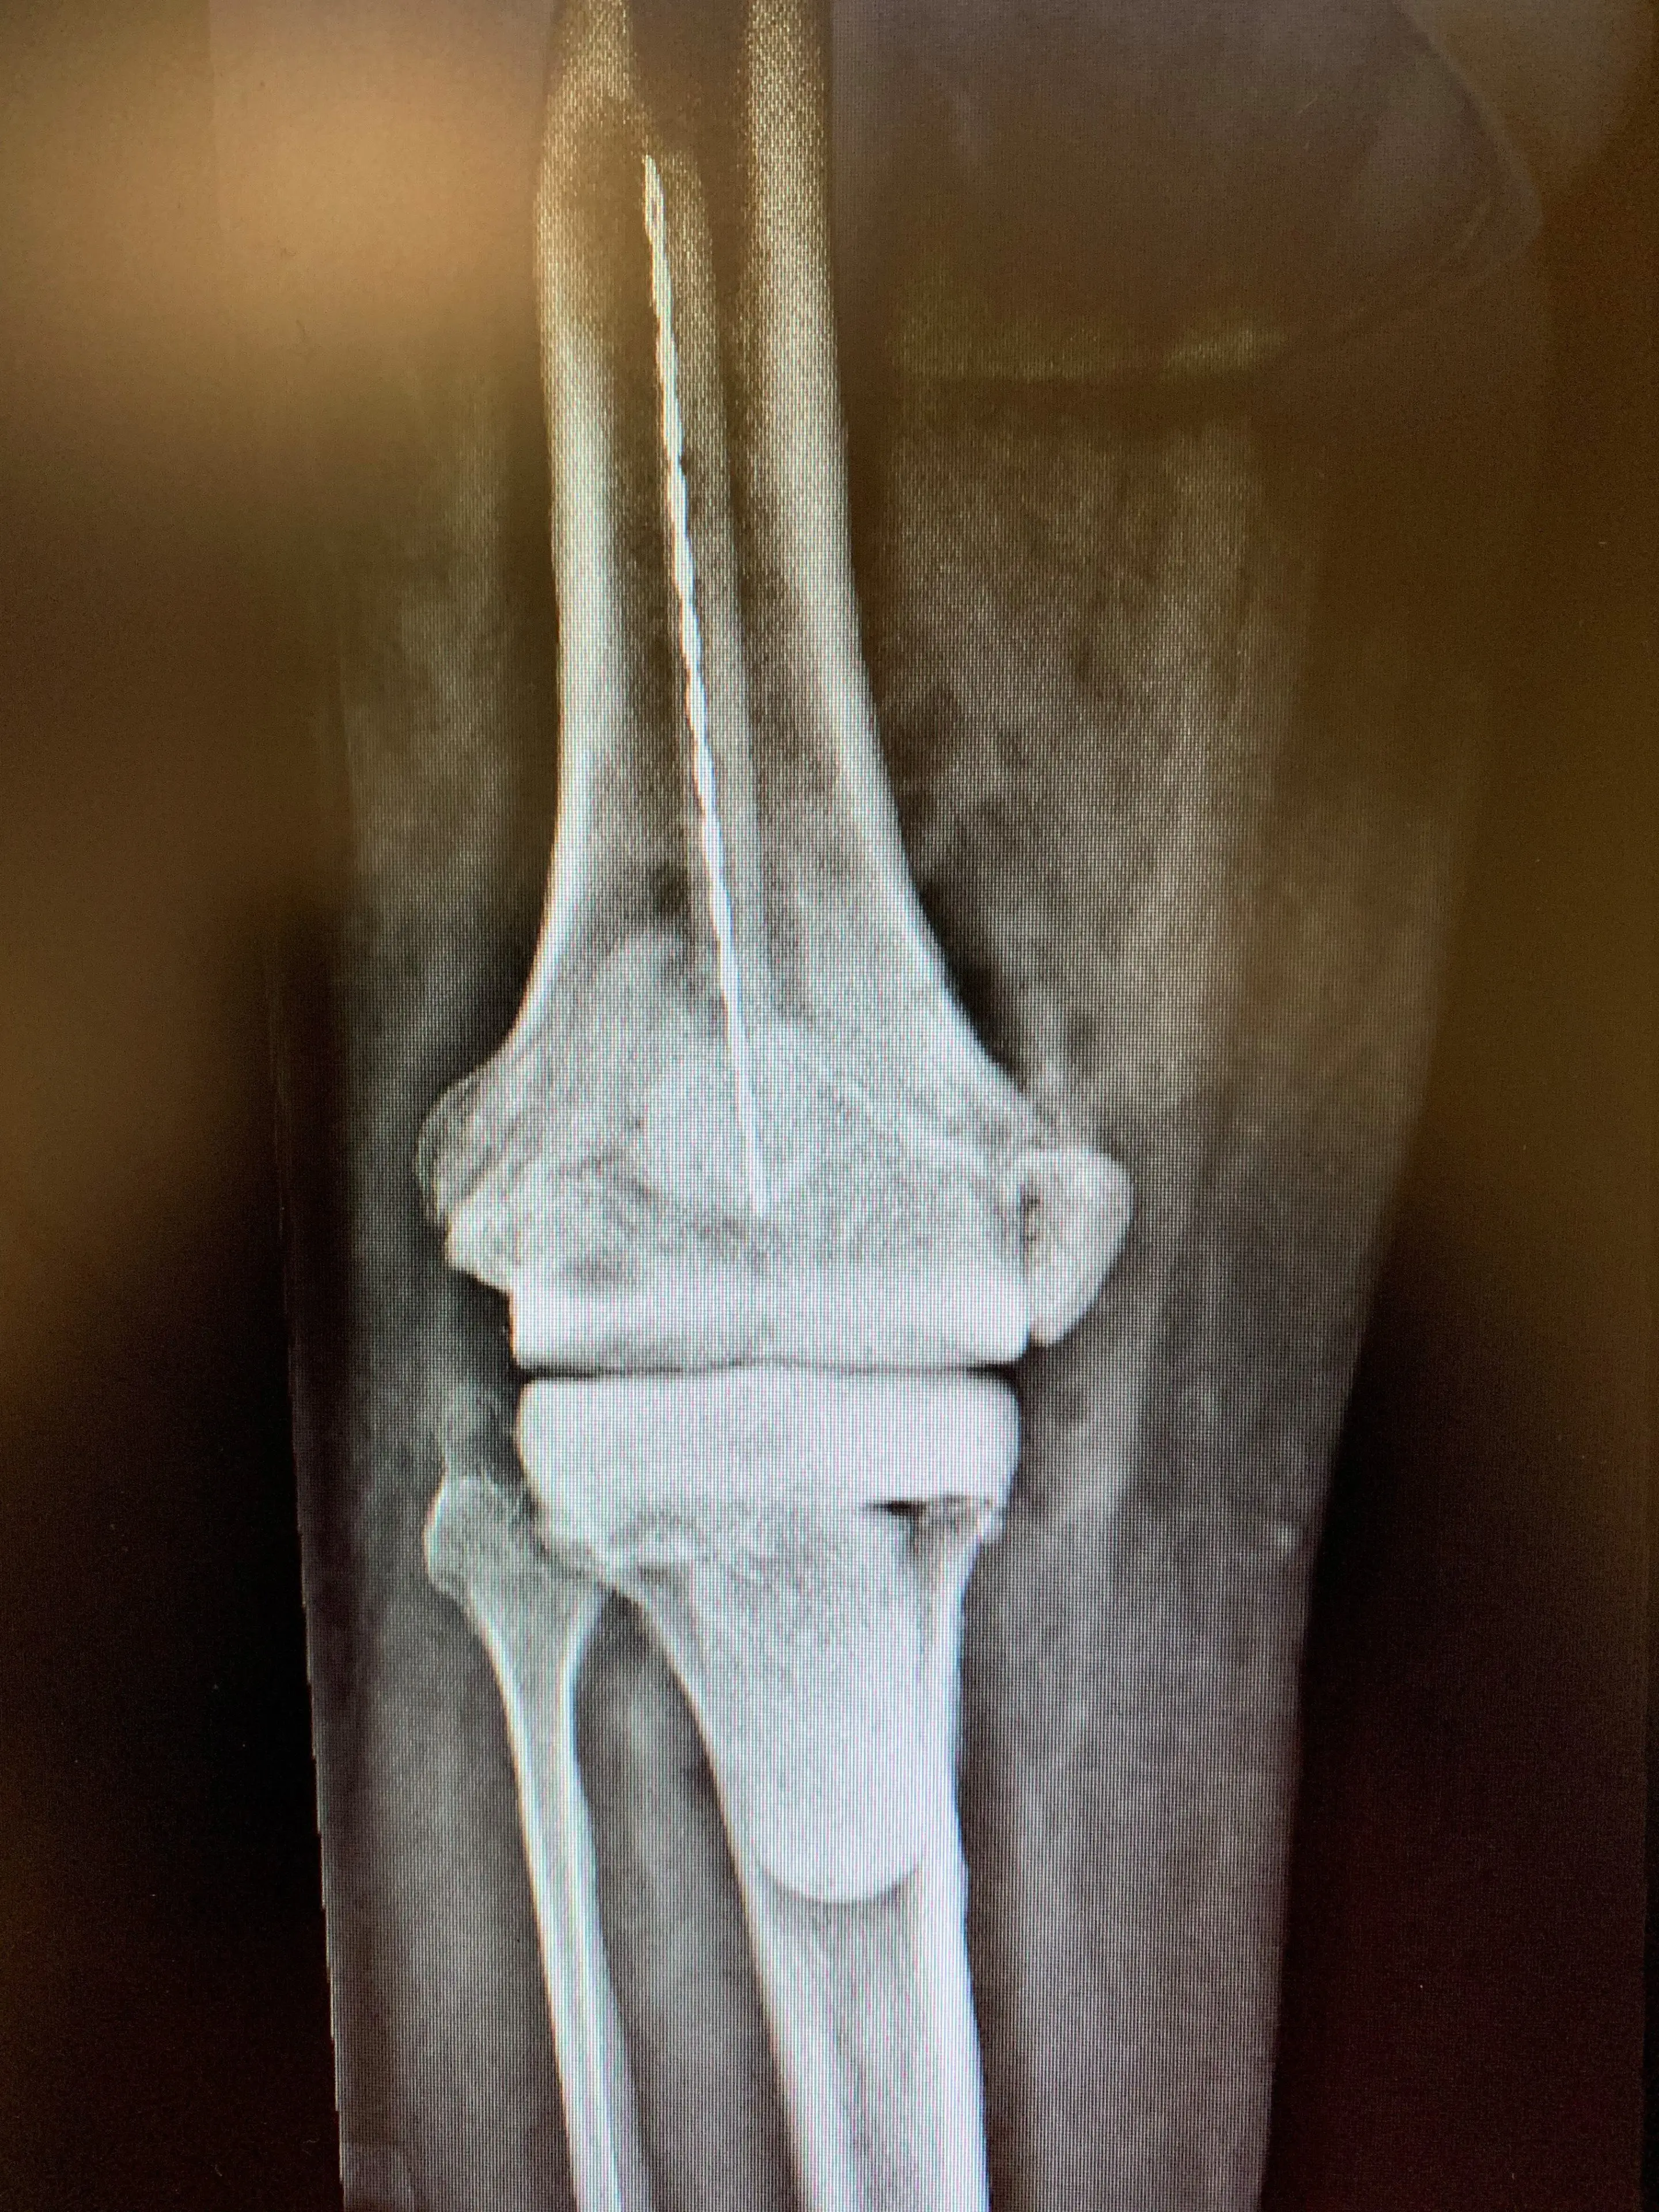

X-rays revealed an appropriately sized and positioned Revision Total Knee Replacement prosthesis with a resurfaced patella and no obvious signs of loosening or periprosthetic fracture.

Pre-opTreatment of infected knee replacement. A staged reconstruction in a 64 year old malea

Treatment of infected knee replacement. A staged reconstruction in a 64-year-old male.